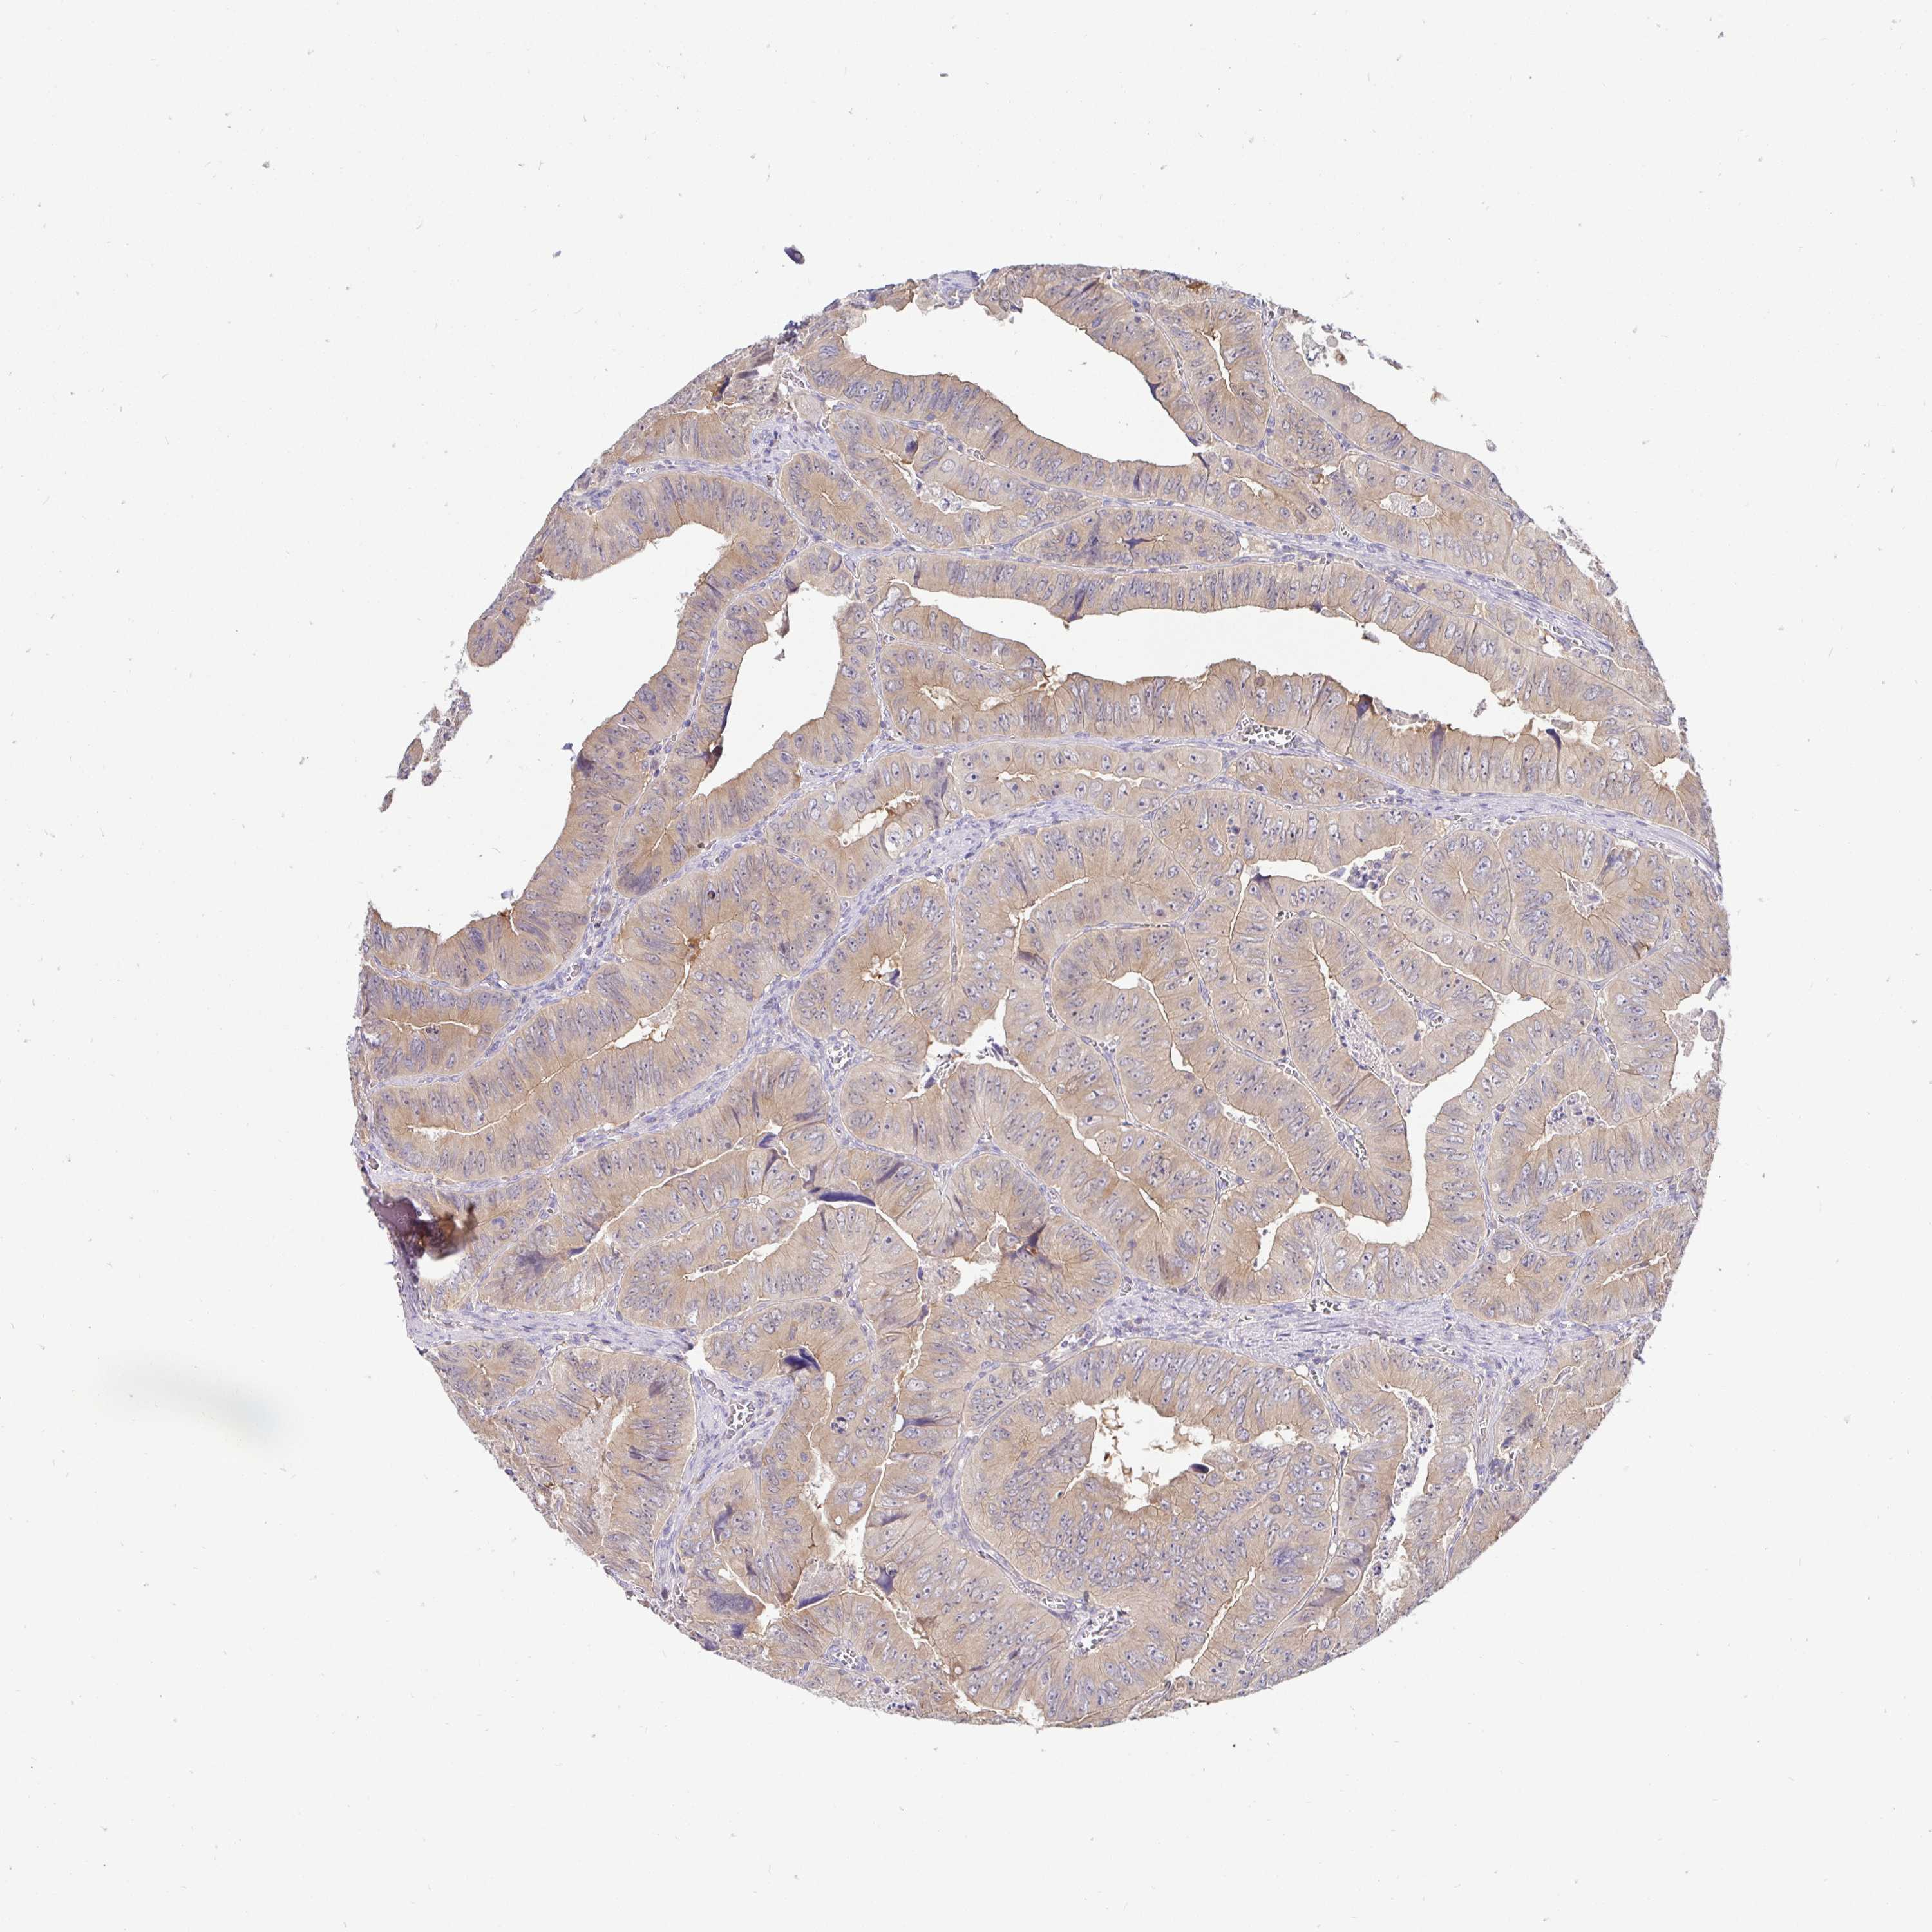

CANCER COLORECTAL CANCER Show tissue menu

Colorectal cancer

Human cancer

Colon adenocarcinoma

RECTUM ADENOCARCINOMA (TCGA) - Interactive survival scatter ploti

KIF21A is not prognostic in Rectum Adenocarcinoma (TCGA)